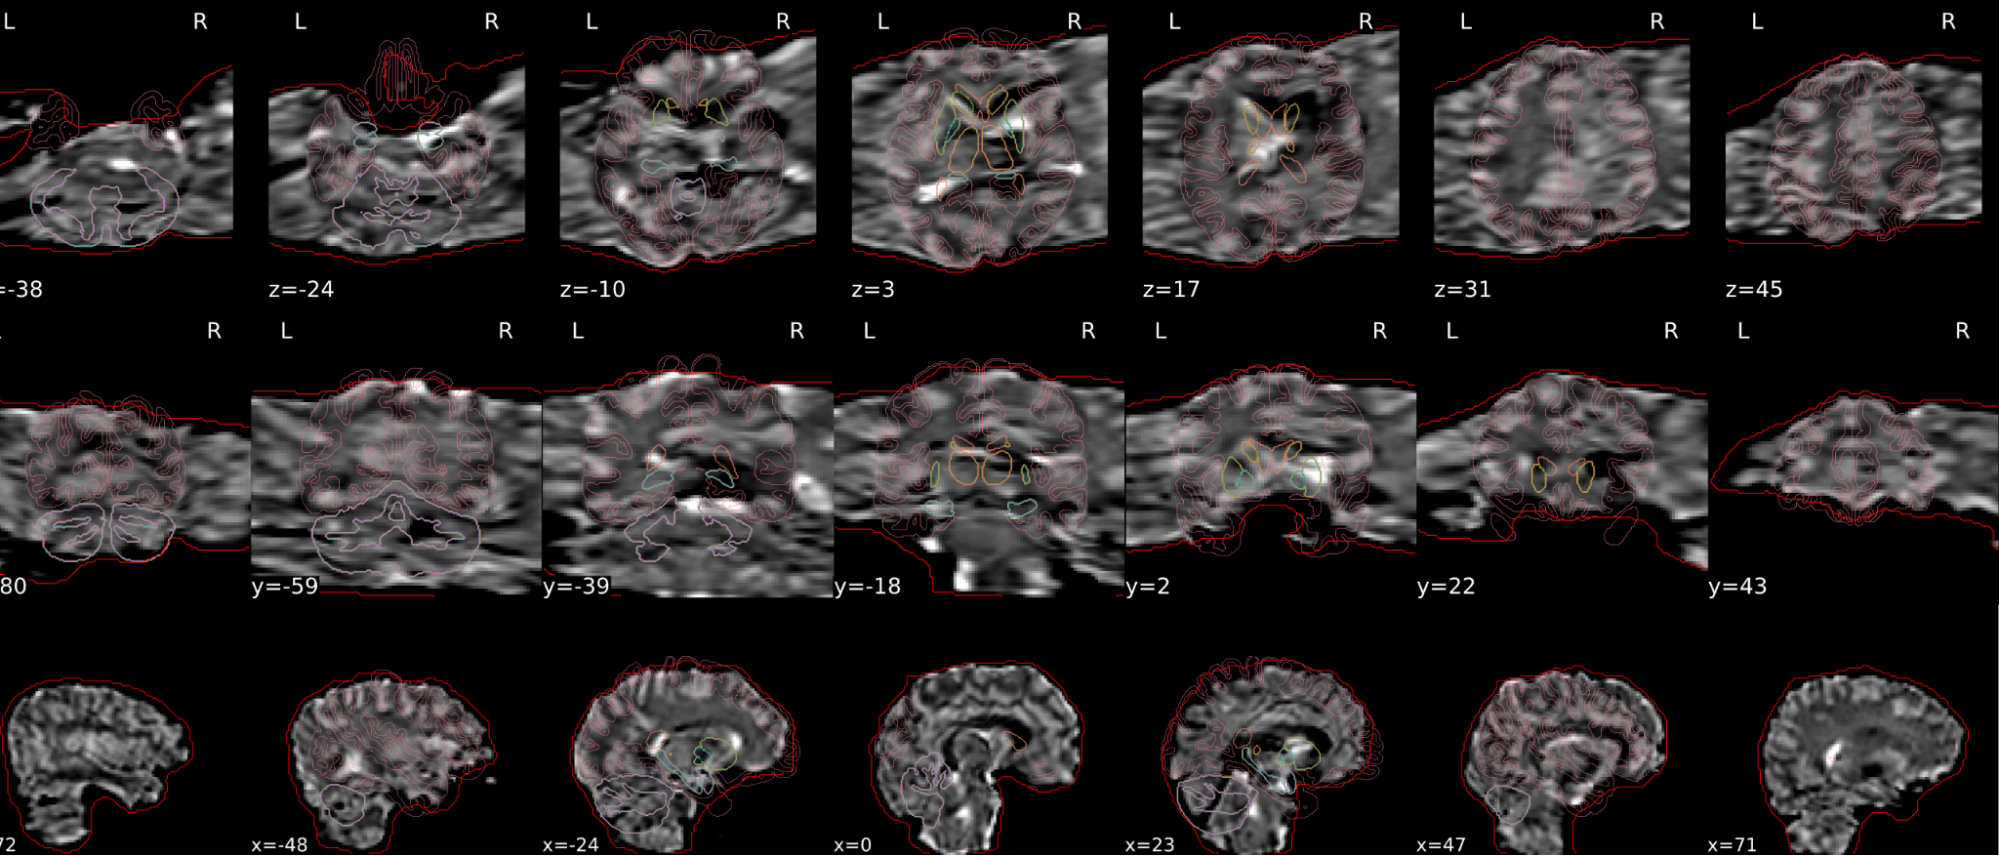

EPI tSNR

In the signal to noise ratio images of the resting state image the desired signal is compared to the amount of background noise. It is important to check all the views (sagittal, coronal, axial) because some artefacts (e.g., stripes) may be evident only in one particular view.

Example of a good subject

- Signal to noise is symmetrically distributed and there is no signal distortion

Example of a bad subject

- Asymmetry

- Potential signal distortion (might represent an artefact)

- Signal drop-out

- Stripes artefact

Clear large artefact (e.g., zebra stripes in example 1) are worth the exclusion of the subject. If you are unsure, check the other quality metrics for that subject to decide whether they should be excluded.

Summary

| good | bad |

|---|---|

| Symmetrical distribution of noise and signal | Asymmetry |

| No disruptions of the signal (no “black patches”) |

Potential signal disruptions (could be related to artefacts) |

| No stripes (sign of high motion) |

Signal drop |

| Stripe artefacts (“zebra” stripes due to motion) |